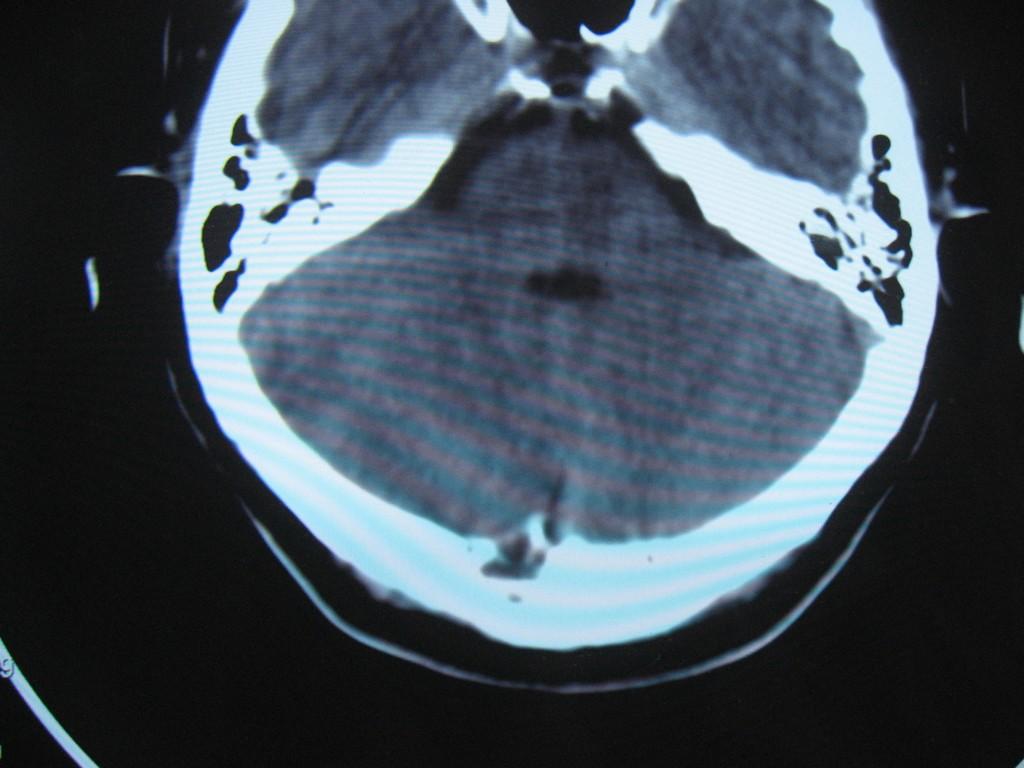

标题: CT22032B:枕骨破坏(从新调整窗宽窗位) [打印本页]

标题: CT22032B:枕骨破坏(从新调整窗宽窗位)

女性病人,53岁,偶尔感枕部针刺样疼痛,ct扫描如下。

蛛网膜颗粒压迹。鉴别:骨巨,嗜酸性肉芽肿,骨髓瘤。

蛛网膜颗粒压迹。

骨巨,嗜酸性肉芽肿,骨髓瘤,动脉瘤样骨囊肿可能

支持蛛网膜颗粒压迹。

支持蛛网膜颗粒压迹,鉴别:骨巨,嗜酸性肉芽肿,骨髓瘤、转移瘤

支持蛛网膜颗粒压迹,嗜酸性肉芽肿发生于30岁以下,基本排除,骨髓瘤、转移瘤多伴有软组织肿块,范围较广。

枕骨蛛网膜颗粒压迹。